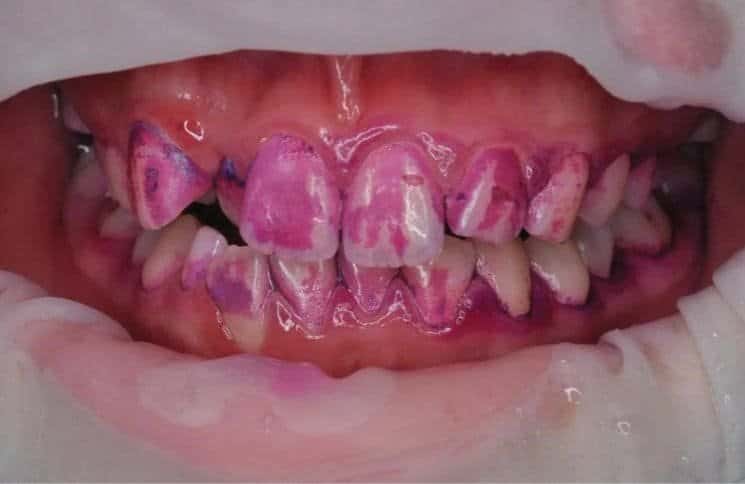

+ 바이오필름 제거에 집중: GBT는 치아와 잇몸에 쌓인 바이오필름(치태)을 제거하는 데 중점을 둡니다. 염색제를 사용해 치태를 시각적으로 확인한 후, 이를 정밀하게 제거하는 과정을 통해 진단과 치료의 정확도를 높입니다(그림 2)

[그림 2] : GBT 염색약을 통해서 치태의 위치를 표시한 상태. 생각보다 많은 치태가 치면에 침착되어있음을 알 수 있다.